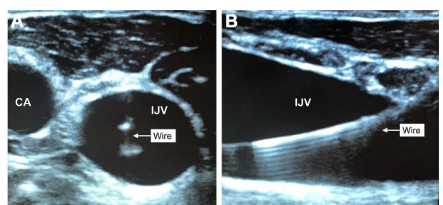

使用超声有助于目视评估目标静脉和邻近结构之间的关系以及扩张前导线在目标血管中的位置(图a和b)。静态超声使操作者能够在手术准备和覆盖之前确定一个适当的、有足够大小的、没有解剖屏障的静脉血管,包括邻近的动脉。它还可以促进病人的最佳定位,如体位,增加颈静脉或锁骨下静脉的横断面积,或减少颈静脉与颈动脉的重叠。然而,单纯的静态超声可能是不够的;静态超声提高了首次插入的成功率,但对于总体成功率和动脉穿刺率却不确定。因此,在操作过程中使用动态超声增加了首次尝试和整体插管成功率,并显著减少了机械并发症、尝试次数、每次插管时间和无意中的动脉穿刺。